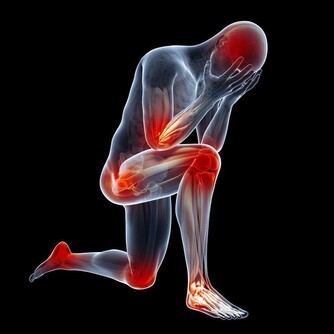

如何把痛風攔在家門外?做好5點

無論屬於何種情況,控制飲食,仍然是預防痛風、控制痛風病情的必要手段。

1.少食高嘌呤食物

如動物內臟、海鮮、火鍋、啤酒等。

2.多食用鹼性食物

如蔬菜、水果、乳製品等,可使尿液鹼化,促進尿酸排出,降低體內的尿酸濃度。

3.多喝白開水

每日飲水量盡量保證2000毫升左右,以促進尿酸的排泄,進而預防尿酸鹽沉積。

4.控制體重

管住嘴,邁開腿,不要貪吃,切莫貪杯。

5. 戒菸限酒

酒精會升高血尿酸,誘發痛風,尤其不建議喝啤酒、白酒;

但適量紅酒並不增加痛風發病率,非發作期可小酌。

吸煙則是代謝綜合徵的高危因素,除了與高血糖、高血壓、高血脂相關,也與高尿酸存在一定關聯,不利痛風人群。